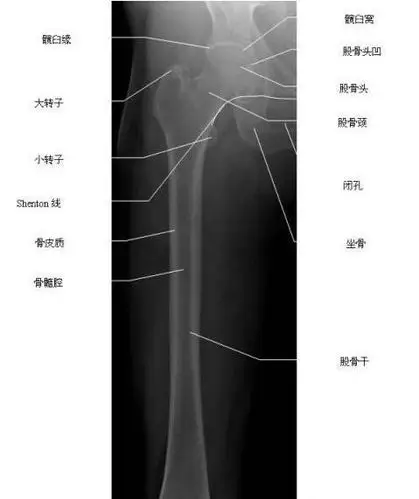

股骨正位-x线图